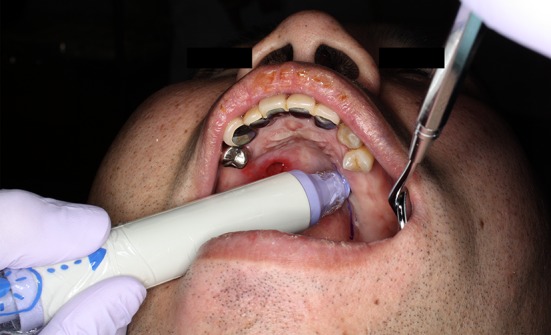

Fig. 3.

Locating the running of the greater palatine artery using a Doppler acouophone

The right greater palatine artery was resected in the initial operation. We designed a mucoperiosteal flap pedicled with the left greater palatine vessel and confirmed this by using a Doppler acouophone along the path of the greater palatine vessel. The patient was asked to open his mouth wide and mouth care gel was applied to the palate, after which the pulsation of the greater palatine artery was auscultated (Fig. 3). We could clearly hear a beat along the greater palatine artery and were able to confirm its position.